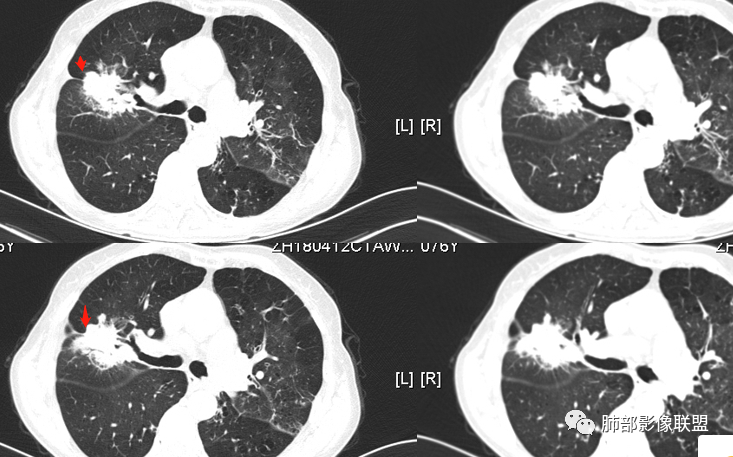

蓝天白云:    老年女性,右肺上叶不规则肿块,月牙铲,有收缩,分叶,毛刺,边缘清晰的磨玻璃影,上叶后段支气管截断,胸膜牵拉凹陷,不均匀延迟强化,内见空泡,纵隔淋巴结增大,IAC。所以的恶性征象都有了

丽:    病灶八年明显增大,右肺上叶不规则肿块,边缘毛刺、分叶,胸膜牵拉,并可见清晰磨玻璃密度影,临近支气管截断,增强后不均匀强化,内可见多发低密度,纵膈肿大淋巴结,考虑恶性,常规考虑腺癌

飞鹰行动:   老年女性,右肺上叶前段结节8年复查明显增大,收缩力较强,有分叶,长短毛刺,邻近胸膜受牵拉,部分支气管截断和受牵拉,周围见边界清晰磨玻璃成分,增强扫描呈不均匀强化,内部低密度区可见磨玻璃强化,边缘模糊,考虑恶性肿瘤,腺癌可能性大。鉴别结核,后者强化不明显,支气管牵拉后扩张。

1、老年女性,肺气肿背景,咯血多年,肿瘤标志物升高。    2、右肺上叶不规则结节影,八年后进行性增大为肿块,边缘深分叶、毛刺、棘状突起、胸膜牵拉,相应支气管壁增厚阻塞;周围局部见边界清楚的磨玻璃影;近胸壁侧见凹陷,整体呈外朝内生长。增强扫描呈不均匀明显强化,其内见坏死区,边界欠清。    3、右侧胸腔积液。纵隔见增大淋巴结。